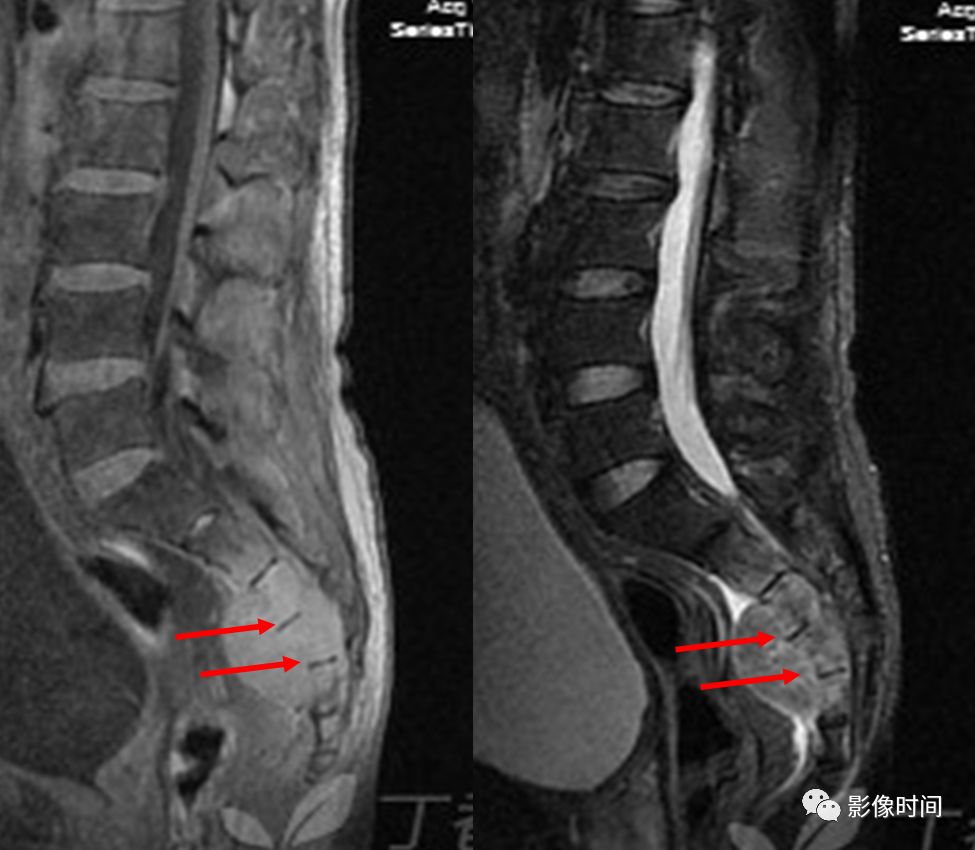

8牙膏征

牙膏征(Toothpaste sign)

牙膏征是指在矢状位脊柱影像中,脱出的椎间盘突入椎管内并向下游走,形似被挤出的牙膏而得名。

典型病例

矢状位 T2WI 像示脱出的椎间盘突入椎管,形似被挤出的牙膏,呈牙膏征(箭示)。